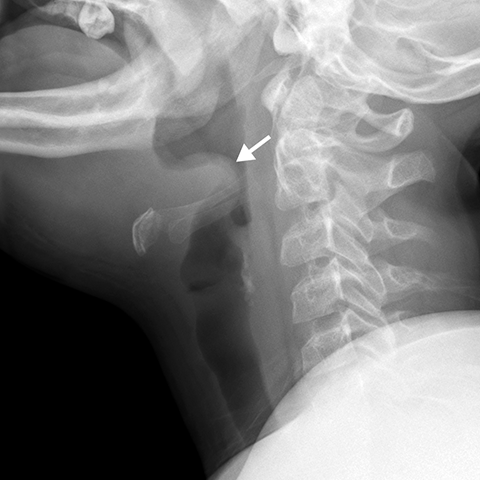

Epiglottitis [2 of 2]